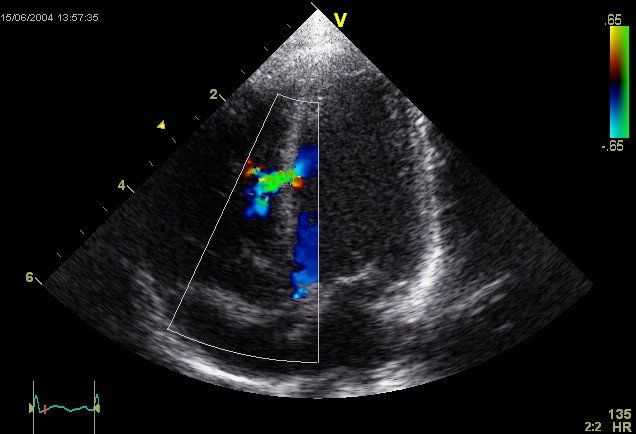

Dr Noor is a Consultant Cardiologist based in London and Surrey. He has expertise in general cardiology including angina (chest pain), syncope (collapse or loss of consciousness), palpitations, hypertension (high blood pressure), hyperlipidaemia (high cholesterol) and valvulopathies (heart valve problems).

He has specialist expertise in diagnosis and treatment of heart failure (symptoms of breathlessness, ankle swelling and fatigue), arrhythmias, Permanent pacemaker (PPM), implantable cardioverter defibrillator (ICD) and cardiac resynchronisation therapy (CRT).